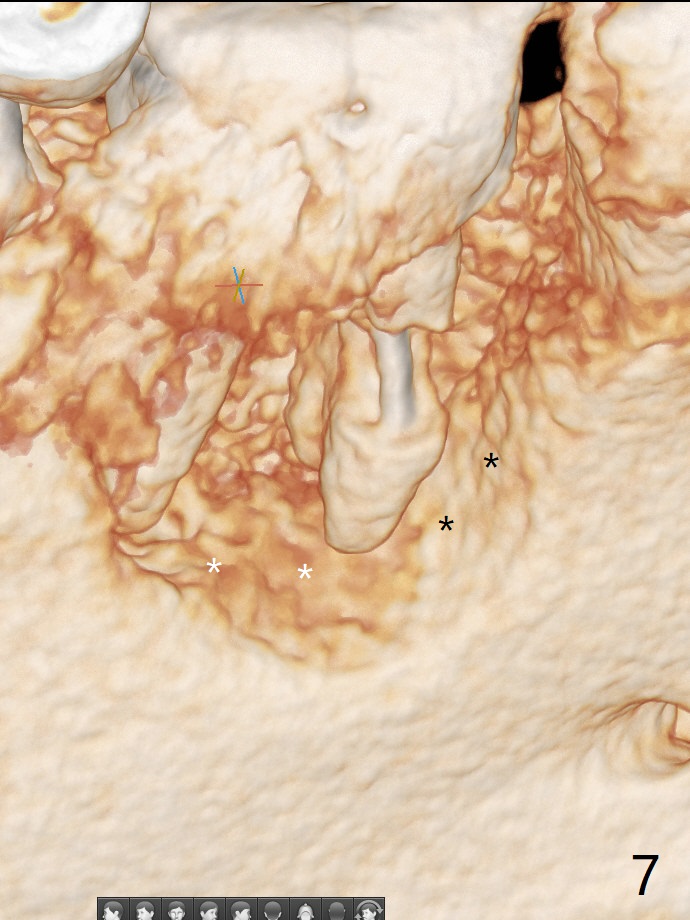

A 47-year-old man has poor dentition. The tooth #31 needs RCT, while #30 has severe PARL, especially mesial (Fig.1 M). The buccal roots are exposed (Fig.2). Between the exposed roots is the septal gingiva, which will be saved for buccal soft tissue repair (Fig.3 *). The septal gingiva will keep in place (not to be transferred) so that the recession will disappear by epithelial regrowth from the nearby gingiva (Fig.3' arrows) over the bone graft and PRF. The provisional should be fabricated to cover the soft tissue defect (Fig.3'' yellow area). In fact the mesial root fractures (Fig.4 ^), as related to the severe bony defect. There seems to be enough lingual bone to hold a 4x13 mm implant (Fig.5 green). Sticky bone (Fig.6 red circles) and PRF (blue) are to be used to repair the hard and soft tissue defects following an immediate provisional (Fig.5,6 yellow outline). Extra layer of acrylic (Fig.6 orange) will be used to cover the PRF buccally. The base of the buccal plate is thick (Fig.6 *); mesial portion appears to be denser (Fig.7 black *) than the distal one (white *). Decortication will be done if hemorrhage is insufficient. Fig.8 is a coronal section of the socket (B: buccal). Extraction (Fig.9 black area) will most likely result in a knife edge ridge. Extraction with bone graft may not fare better, as it is easy to lose the graft considering missing buccal hard and soft tissues.